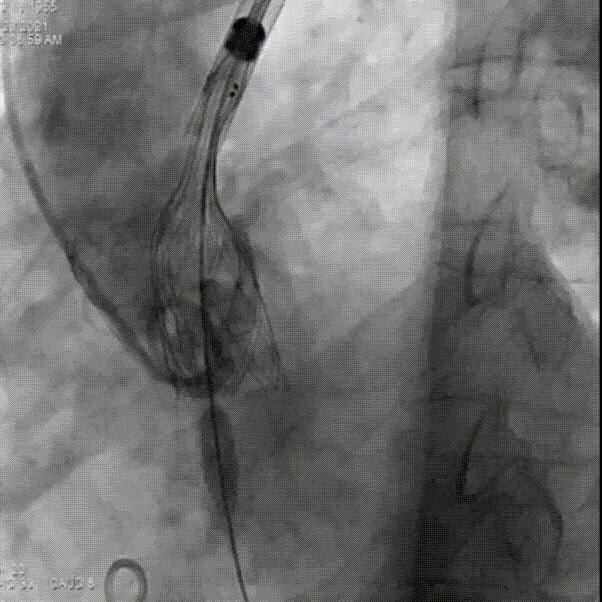

完全释放后,主动脉根部造影

术后超声:

术后压差显著改善,无反流,患者血压良好。

植入后心衰及血流动力学都有效改善,术后Vmean1.6M/S,Pgmean 7mmHg。